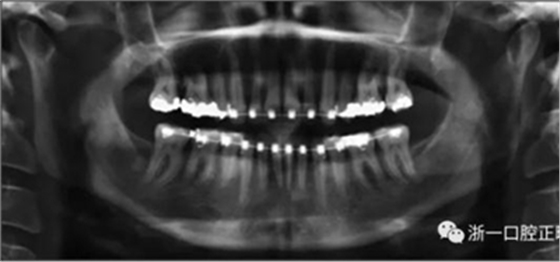

術(shù)后第9天開始旋轉(zhuǎn)擴弓器,每天轉(zhuǎn)2次,每次轉(zhuǎn)90度,即擴開0.5mm。每隔1周進行檢查,目標上頜擴開9mm,下頜擴開6mm。18天后,上頜中切牙間出現(xiàn)8mm間隙。下頜出現(xiàn)6mm間隙,(于13天出現(xiàn)后,停止旋轉(zhuǎn)擴弓器)。在擴弓器旋轉(zhuǎn)3天后,拍片發(fā)現(xiàn)左下頜中切牙遠中牙根中段有一條低密度陰影,臨床冷熱診反應(yīng)遲鈍,可能為術(shù)中損傷所致。牙體牙髓科會診,建議行根管治療,故行根管治療。

擴弓保持8周后,除擴弓器影響牙外粘接托槽,使用0.014鎳鈦絲進行排齊、整平。旋轉(zhuǎn)停止后3個月拆除擴弓器,全口粘接托槽,使用0.016niti繼續(xù)排齊整平。佩戴可摘保持器,保持上頜寬度。在使用至0.018x0.018niti7周,徹底排齊整平后,使用大弓型的0.016x0.022不銹鋼絲,繼續(xù)維持原有寬度,同時停止使用可摘保持器。掛II類牽,糾正磨牙關(guān)系,使用鏈圈關(guān)閉散在間隙,少量使用IPR去除局部前牙的黑三角。術(shù)后9個月拍全景示,牙根平行度可,再無其他牙根出現(xiàn)問題。1年7個月后治療結(jié)束。上下頜3-3舌側(cè)保持器+哈雷氏保持器進行保持。